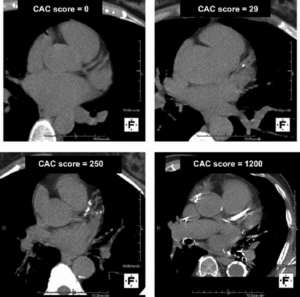

A calcium score is a number that is calculated from a calcium scan, which is a CT scan of the heart. The CT scan takes only a few moments to complete. Importantly, calcium on CT scans show up as white while other tissue (the heart muscle, the walls of arteries and veins, etc.) show up as various shades of gray. We can count how large the area of white calcium is on the CT scan. We then compare the area of calcium to age-matched individuals through a database of hundreds of thousands of subjects to determine how much calcium a patient has compared to the average person their age. Higher numbers are worse; it demonstrates that there has been more damage done to the arteries of the heart and helps predict who is at the greatest risk of heart attacks over the next few years to decades.